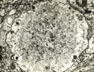

Fig 34a - Lafora bodies in the liver.

Diastase-PAS Stain.

(From G. Klatskin &

H.O. Conn Histopath.

of the liver)